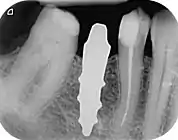

A new attempt was made by Pirker et al 2004 in a human trial with root analogue zirconia implants, but this time by applying differentiated osseoingration on the surface. In 2011 he reported 90% success rate with this method in a 2.5 year human trial.[11]

Mangano et al in Italy in 2012 reported the successful clinical use of a custom-made root analogue implant made by direct laser metal forming (DLMF) from a CBCT scan. This demonstrated that it is possible to combine CBCT 3D data and CAD/CAM technology to manufacture root-analogue implants with sufficient precision.[24]

- ↑ Pirker, W; Kocher, A (2008). "Immediate, non-submerged, root-analogue zirconia implant in single tooth replacement". International Journal of Oral and Maxillofacial Surgery. 37 (3): 293–5. doi:10.1016/j.ijom.2007.11.008. PMID 18272340.

- ↑ Pirker, W; Kocher, A (2009). "Immediate, non-submerged, root-analogue zirconia implants placed into single-rooted extraction sockets: 2-year follow-up of a clinical study". International Journal of Oral and Maxillofacial Surgery. 38 (11): 1127–32. doi:10.1016/j.ijom.2009.07.008. PMID 19665354.

- 1 2 3 Pirker, W; Wiedemann, D; Lidauer, A; Kocher, A (2011). "Immediate, single stage, truly anatomic zirconia implant in lower molar replacement: a case report with 2.5 years follow-up". International Journal of Oral and Maxillofacial Surgery. 40 (2): 212–6. doi:10.1016/j.ijom.2010.08.003. PMID 20833511.